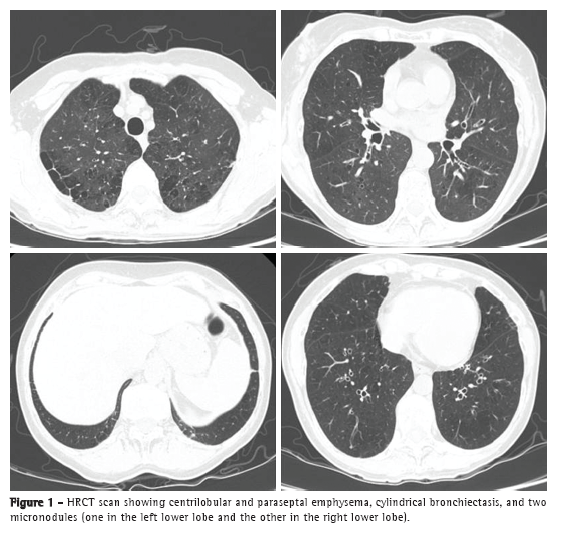

An HRCT scan showed centrilobular and paraseptal emphysema, cylindrical bronchiectasis (predominantly central and upper lobe bronchiectasis), and two micronodules of 3 mm and 4 mm in diameter, respectively, in the right lower lobe and in the left lower lobe (Figure 1). Immunoglobulin quantification showed an increase in total IgE levels (671 IU/mL), with no other abnormalities. Alpha-1 antitrypsin levels were normal. Respiratory function test results revealed moderately severe obstructive lung disease accompanied by inflation, moderately reduced alveolar-capillary diffusion, and mild type I respiratory failure. The patient had a negative bronchodilator response (Table 1). Her electrocardiogram was normal, and the results of the microbiological study of sputum were negative.